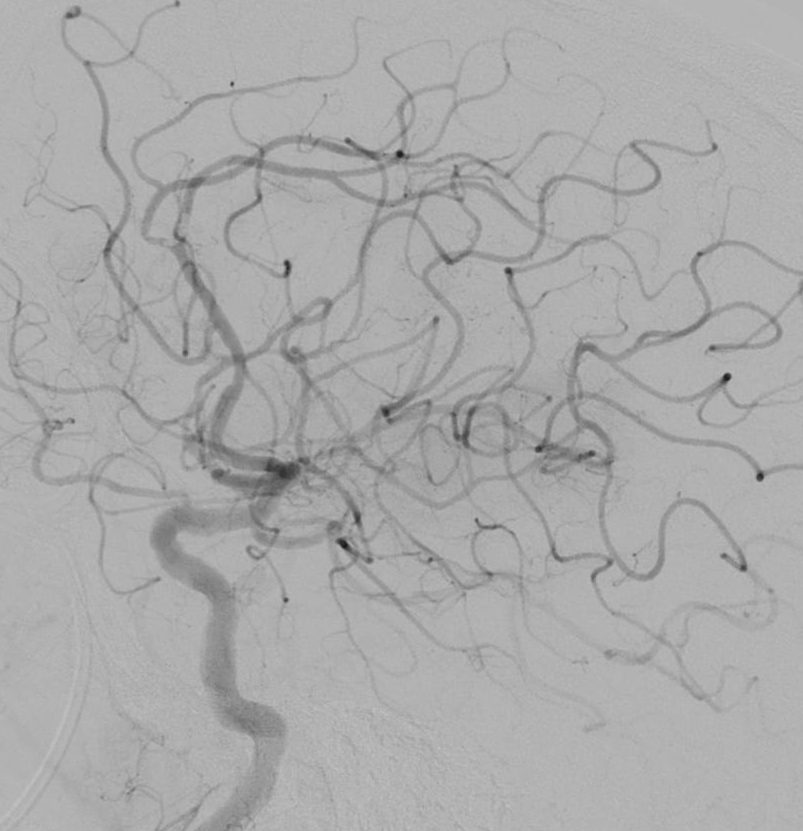

Lors de cette intervention réalisée par des radiologues spécialisés, un cathéter est inséré dans le réseau artériel, généralement par une piqure dans l’aine, et guidé jusqu’aux artères du cerveau, où il permet de retirer mécaniquement le caillot qui bloque la circulation sanguine à l’aide d’un stent et/ou d’un cathéter d’aspiration. Cette procédure vise à restaurer le flux sanguin vers la zone du cerveau affectée, minimisant ainsi les dommages cérébraux et améliorant les chances de récupération. L’intervention est réalisée sous contrôle radiologique en temps réel.